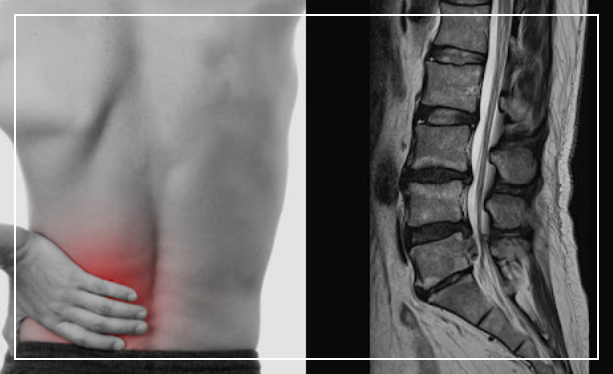

허리디스크는 척추뼈 사이의 디스크가 튀어나와서 신경을 압박하는 질환인데요, 초기에는 단순 요통으로 생각하고 넘기기 쉽지만 방치하면 일상생활이 힘들어질 수 있어요.

허리디스크의 가장 기본적인 증상은 바로 허리 통증이에요. 허리 한가운데나 한쪽에서 묵직하고 뻐근한 통증이 느껴지는데, 처음에는 가볍게 시작해서 점점 심해지는 경향이 있어요. 특히 아침에 일어날 때나 오래 앉아있다가 일어설 때 통증이 더욱 심하게 느껴지죠.

기침이나 재채기를 할 때도 허리에 찌릿한 통증이 올라오는 경우가 많아요. 이런 통증은 며칠 쉬면 나아지기도 하지만, 재발이 잦고 점점 더 악화되는 특징이 있으니 가볍게 생각하지 마시고 전문의와 상담해보시는 게 좋아요.